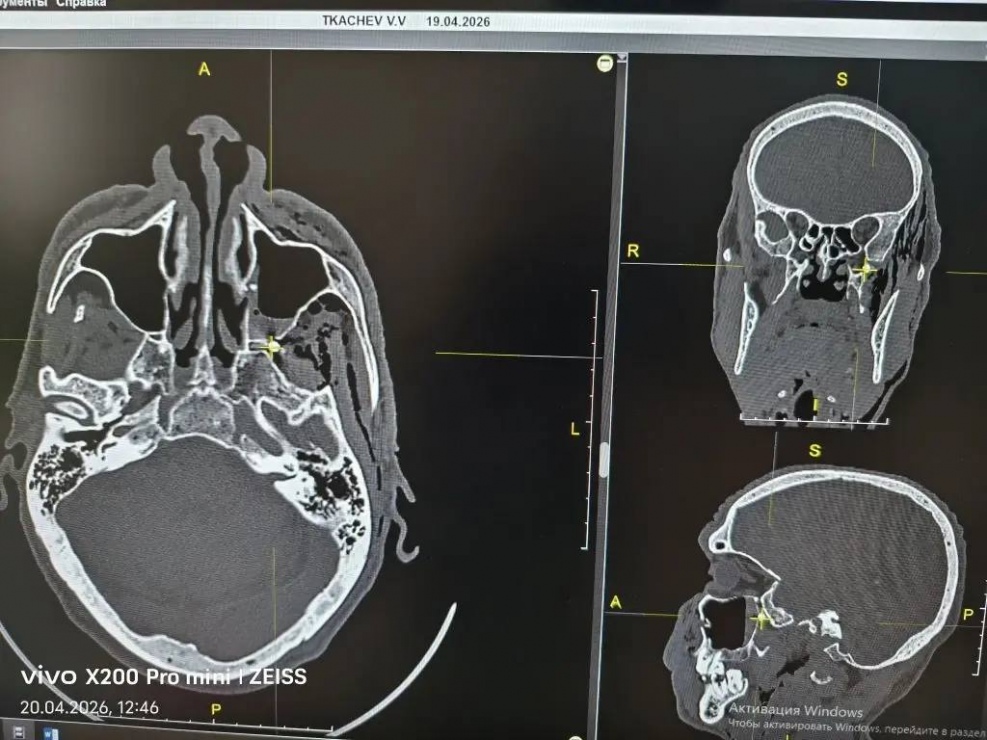

Врачи тщательно обследовали пациента и установили, что пуля прошла через переднюю и заднюю стенки верхнечелюстной пазухи, застряв в крыло-нёбной ямке, и извлечь ее весьма сложно. Это «узел связи» внутри черепа, расположенный за верхней челюстью, через который проходят нервы и сосуды. Крыло-нёбная ямка соединяется с глазницей, полостью рта, носа, черепа и областью под скулой.

Заведующей лор-отделением хирургического стационара Татьяне Смирновой предстояло провести дессекцию крыло-небной ямки — раздвинуть слои ткани и вытащить пулю. Одно неловкое движение и началось бы сильнейшее кровотечение.